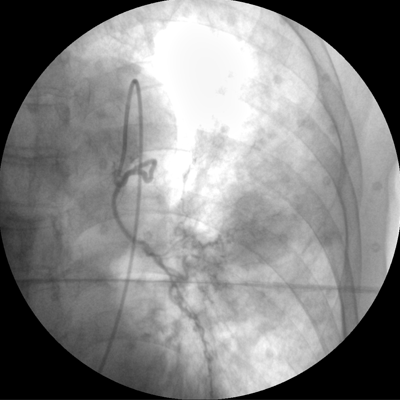

四維電動(dòng)運(yùn)動(dòng)控制,平滑定位,使得復(fù)雜角度快速實(shí)現(xiàn)。

專業(yè)的圖像處理系統(tǒng),為您提供高分辨率、高灰階圖像。